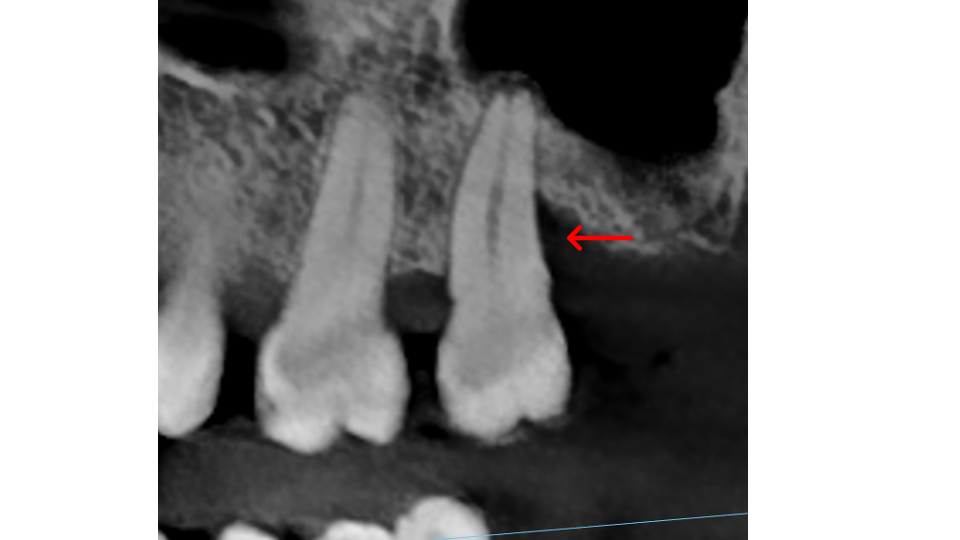

Root grooves: All teeth with multiple roots have grooves running along them. In some patients these grooves are deeper than average, creating sheltered pockets where bacteria hide and accumulate. Premolars can have grooves extending far below the gum line, making them especially challenging to keep clean.

Furcations: This is the area where the roots of a multi-rooted tooth divide. Lower molars have one furcation (two roots); upper molars have three furcations (three roots). When bone loss reaches the furcation, disease spreads through the tooth, not just around it, creating undercuts that trap bacteria and make the area extremely difficult to clean without surgical access.

Bone thickness and shape: Bacteria on your teeth can only cause bone destruction within about 1.5 mm of where they sit, referred to as their "sphere of influence." When the surrounding bone is thin or roots are very close together, bacteria can destroy the bone completely, leading to gum recession and more exposed tooth surface. In these cases, non-surgical therapy is often sufficient. When bone is thick, bacteria can only destroy part of it, creating craters or "moats" around the tooth. These craters cannot be fully cleaned with non-surgical treatment and typically require surgery to correct.

- X-Rays (Radiographs): X-rays show the pattern and extent of bone loss. We can see whether bone has been lost evenly (horizontal loss) or whether craters and vertical defects have formed. This pattern directly determines which type of treatment you need.